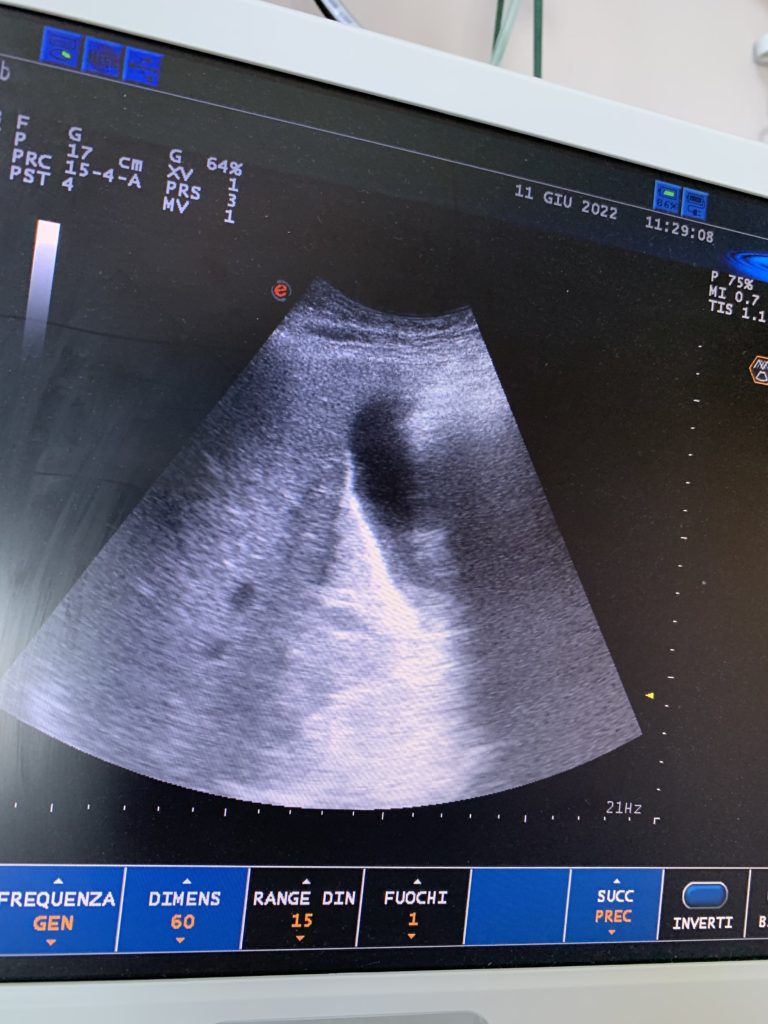

Il mio fegato, il diaframma ed i polmoni.

Ecografia a letto per controllare la respirazione cardiaca accettarata da stamattina.

È tutto nella norma.